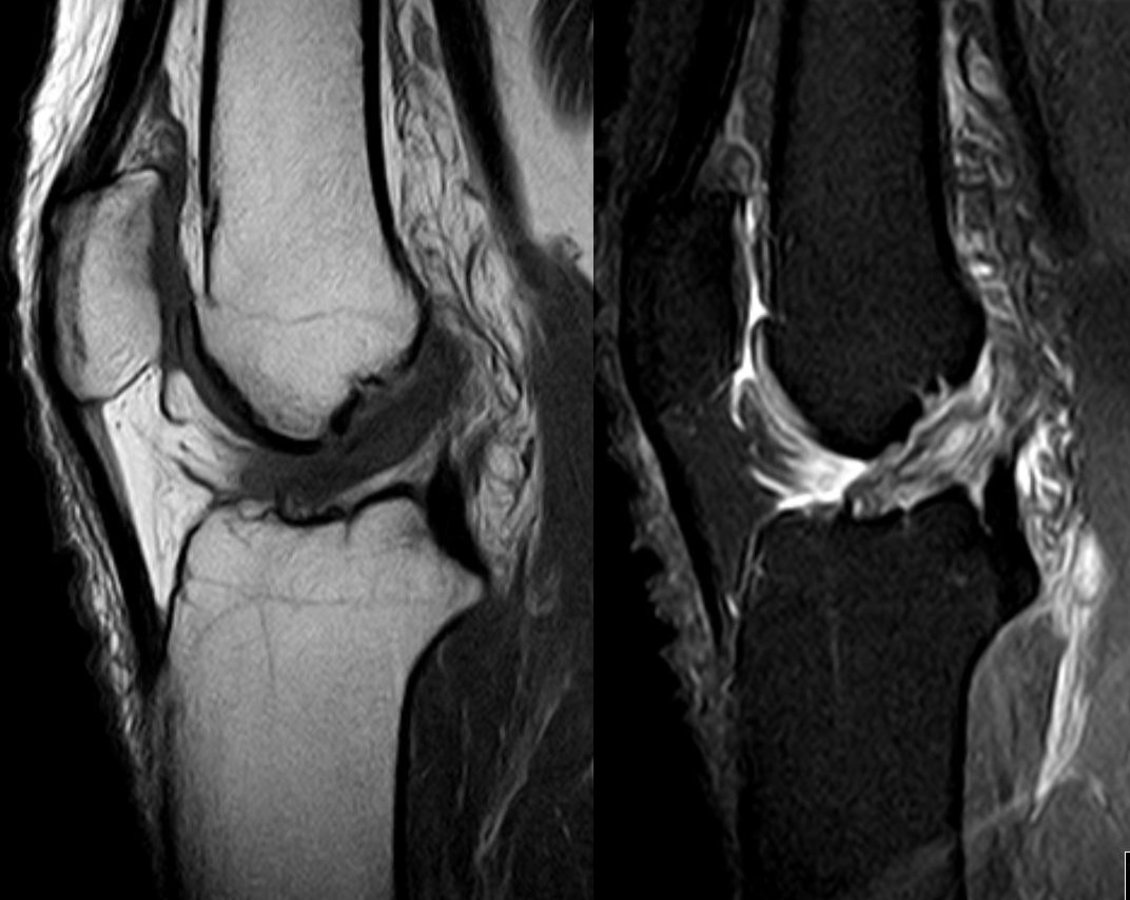

Nur selten schaffen die Sportler es nach einem Kreuzbandriss wieder langfristig auf den Platz. Knieprobleme bleiben auch nach einer OP. Nur selten schaffen die Sportler es nach einem Kreuzbandriss wieder langfristig auf den Platz. Knieprobleme bleiben auch nach einer OP. © wikimedia/Hellerhoff; wikimedia/Ageekgal

Ein Vorderer Kreuzbandriss in der Magnetresonanztomographie. Ein Vorderer Kreuzbandriss in der Magnetresonanztomographie. © wikimedia/Hellerhoff